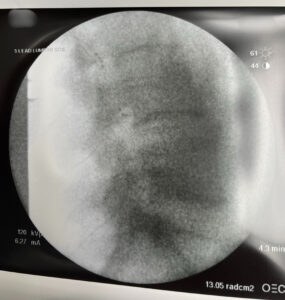

Dr. Suneil Jolly, Medical Director of Louisiana Pain Specialists, recently completed a highly complex dorsal root ganglion procedure. With the help of the ProclaimTM DRG System from Abbott, this procedure is expected to produce a complete quality of life upgrade for the receiving patient.

The receiving patient had suffered from chronic nerve pain after a crush injury. The use of the DRG implant provides targeted pain relief to the area producing an improved quality of life. This procedure has also enabled the patient to avoid costly back surgery while returning them to a more normal function of their everyday life.